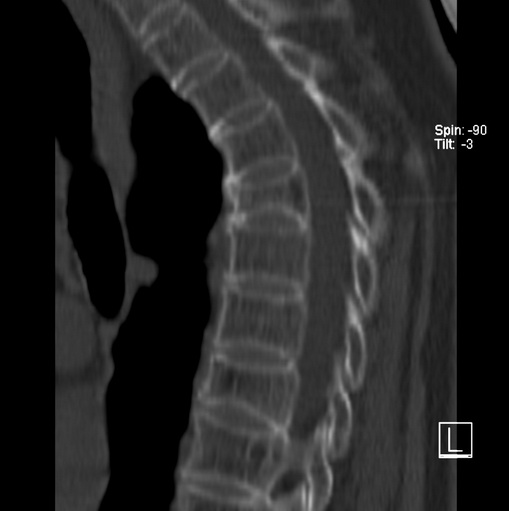

女、73、胸痛、胸闷3个月,无明显外伤病史,x线疑t4、t7陈旧压缩骨折,ct未经明显骨折,请问结论如何报?

老年女性病人,骨质稀疏,有些驼背,t4明显变扁,t7略变扁,椎体边缘无中断,骨小梁排列正常,无嵌插所致致密线。结合无明显外伤史,考虑老年骨质稀疏,慢性压缩改变,正如老年人骨质稀疏椎体呈双凹改变一样。我考虑报:老年骨质稀疏,t4、t7楔形变,脊柱曲度改变(驼背).敬请大家指教。